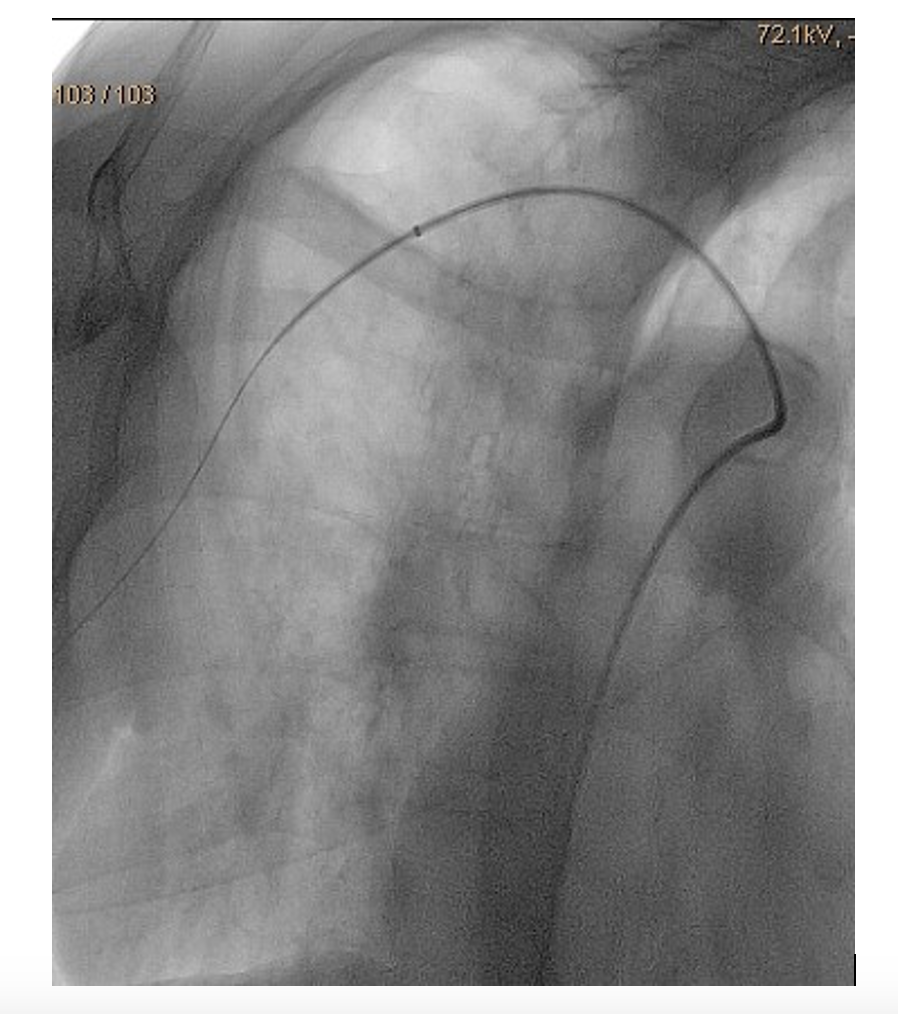

A 6 Fr/90 cm Fortress introducer sheath (Biotronik) was placed at the right subclavian artery (Figure 3). Recanalization was done with a 0.018" Glidewire Advantage (Terumo) and a Trail Blazer Angled Support Catheter (Medtronic) (Figure 4). Balloon dilatations were done with a 2/120 mm Passeo-18 (Biotronik) and a 3/120 mm Passeo-18, without effect (Figure 5). Then, a 0.014" Fielder wire (Asahi) was placed to the palmar arch. Thromboaspiration of red thrombotic masses was done with a 6 Fr Eliminate aspiration catheter (Terumo). Again, there was no distal flow.